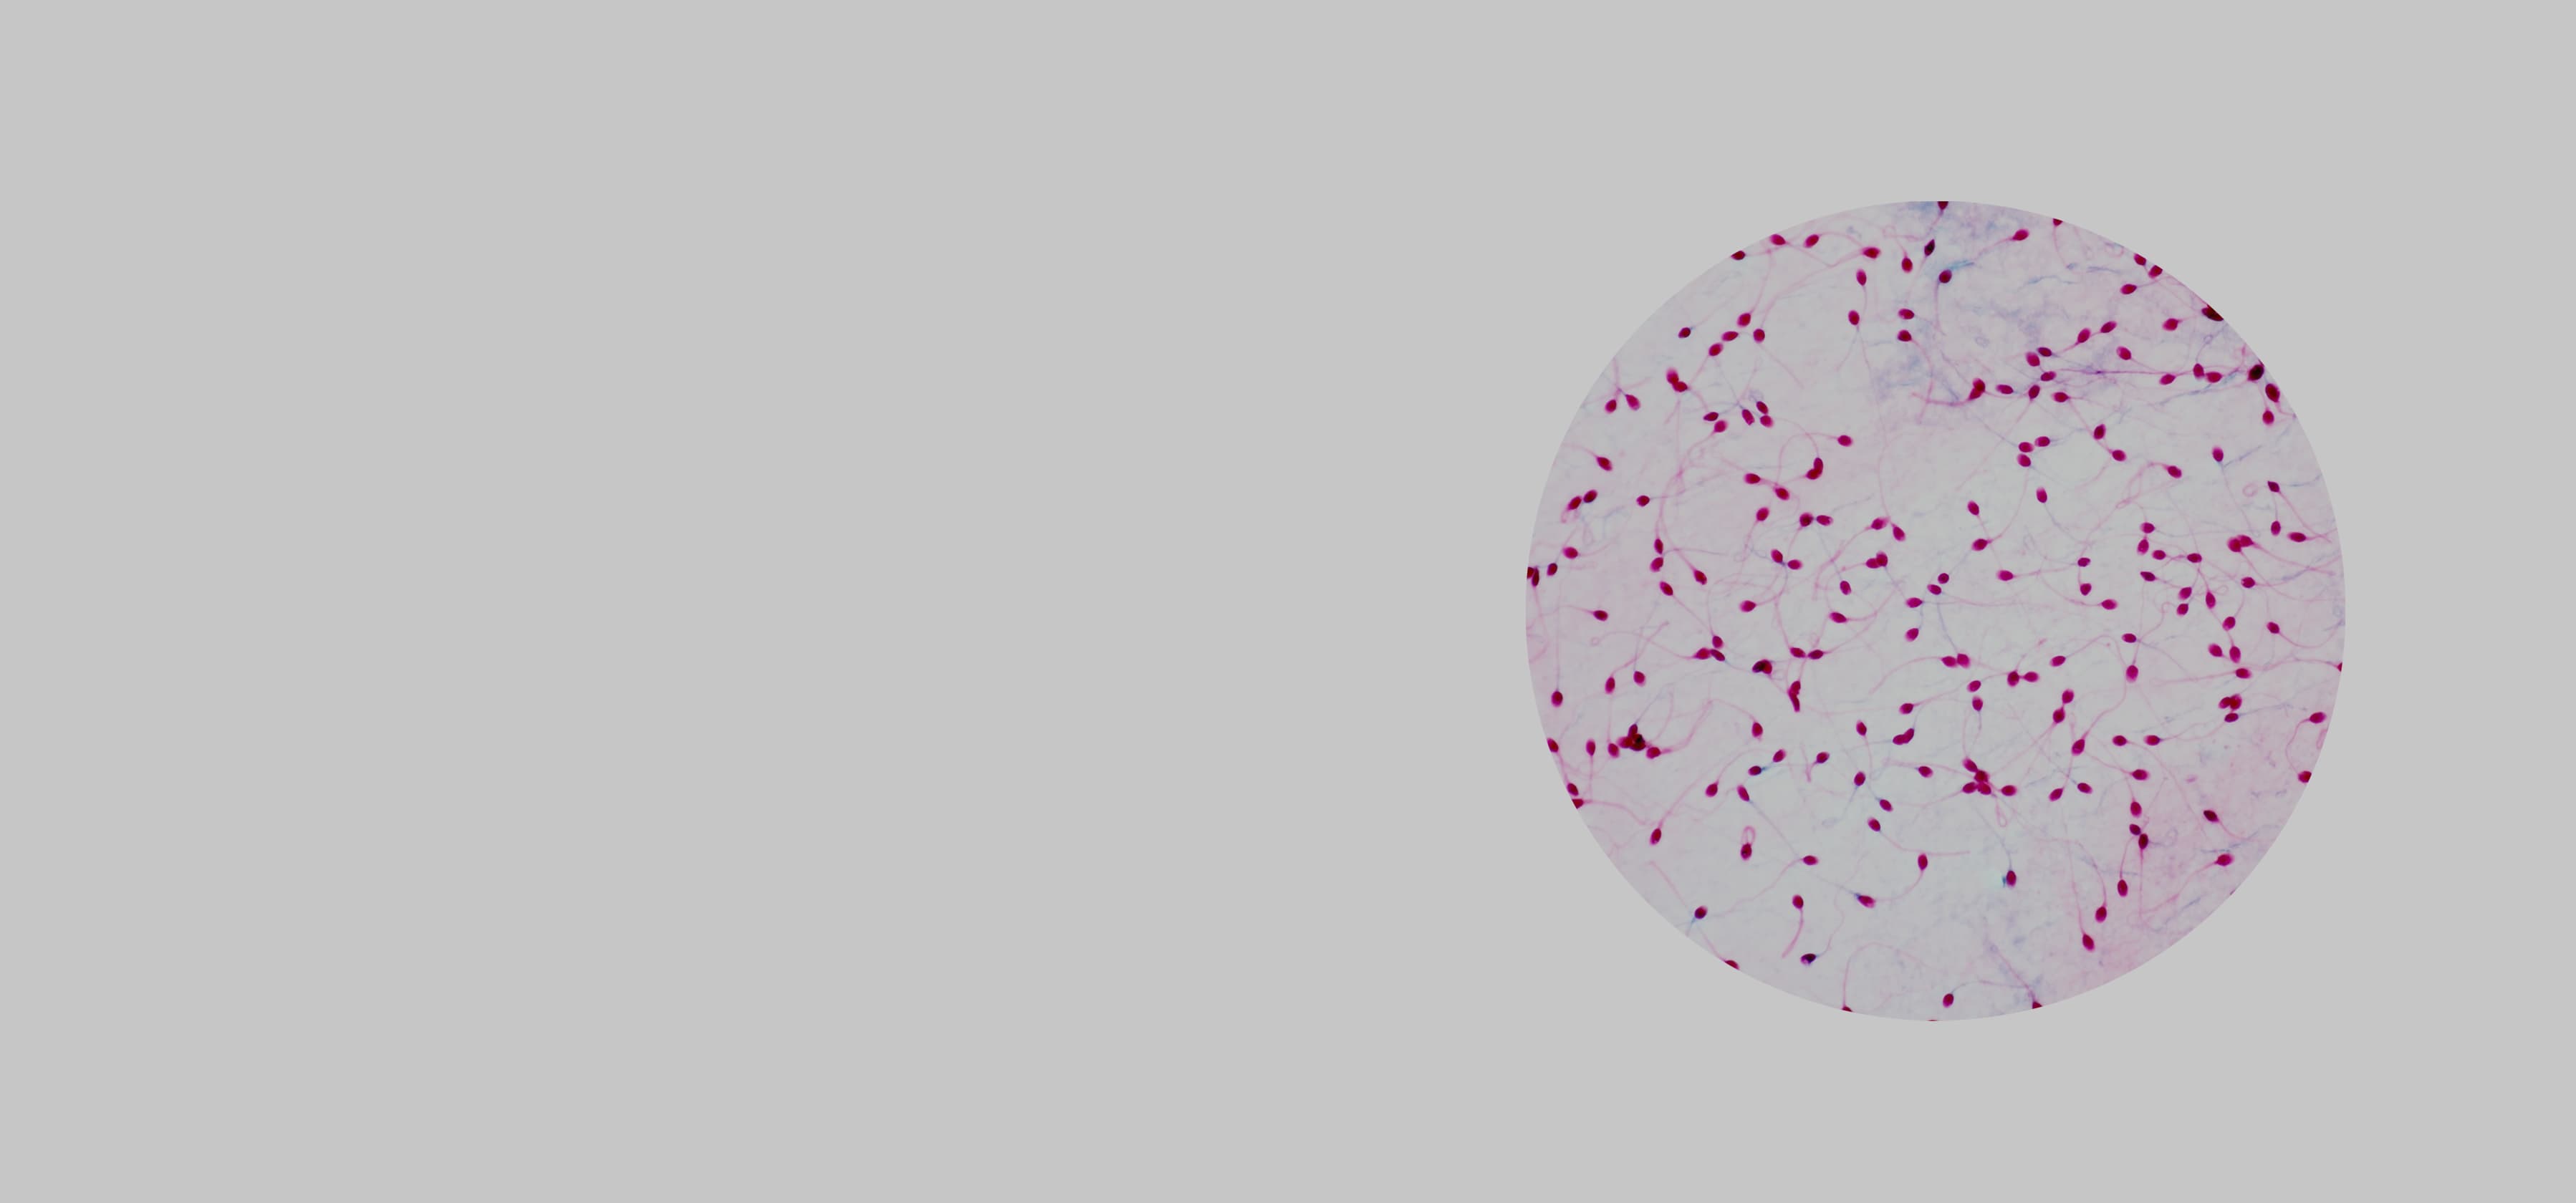

Спермограмма — это базовый анализ спермы, который позволяет оценить макроскопические (объем, ph и др.) и микроскопические (число сперматозоидов, а также подвижность и морфологию сперматозоидов) параметры.

Спермограмма — это анализ спермы. С помощью данного анализа можно оценить функцию половых органов и проходимость семявыносящих путей, а также определиться с дальнейшей тактикой обследования. С ее помощью можно выявить отсутствие сперматозоидов в эякуляте, недостаточную подвижность и концентрацию, заподозрить воспалительные заболевания половых органов и так далее.

Базовый анализ эякулята (спермограмма) учитывает важные параметры эякулята: объем, вязкость, концентрацию сперматозоидов, их подвижность и морфологию.